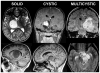

Object: Thalamopeduncular tumors arise at the junction of the inferior thalamus and cerebral peduncle and present with a common clinical syndrome of progressive spastic hemiparesis. Pathologically, these lesions are usually juvenile pilocytic astrocytomas and are best treated with resection with the intent to cure. The goals of this study are to define a common clinical syndrome produced by thalamopeduncular tumors and to discuss imaging characteristics as well as surgical adjuncts, intraoperative nuances, and postoperative complications relating to the resection of these neoplasms.

Methods: The authors present a retrospective review of their experience with 10 children presenting between 3 and 15 years of age with a thalamopeduncular syndrome. Formal preoperative MR imaging was obtained in all patients, and diffusion tensor (DT) imaging was performed in 9 patients. Postoperative MR imaging was obtained to evaluate the extent of tumor resection. A prospective analysis of clinical outcomes was then conducted by the senior author.

Results: Pilocytic astrocytoma was the pathological diagnosis in 9 cases, and the other was fibrillary astrocytoma. Seven of 9 pilocytic astrocytomas were completely resected. Radical surgery was avoided in 1 child after DT imaging revealed that the corticospinal tract (CST) coursed through the center of the tumor, consistent with the infiltrative nature of fibrillary astrocytoma as identified by stereotactic biopsy. In 8 patients, tractography served as an important adjunct for designing a surgical approach that spared the CST. In 6 cases the CSTs were pushed anterolaterally, making a transsylvian approach a poor choice, as was evidenced by the first patient in the series, who underwent operation prior to the advent of tractography, and who awoke with a dense contralateral hemiparesis. Thus, subsequent patients with this deviation pattern underwent a transcortical approach via the middle temporal gyrus. One patient exhibited medial deviation of the tracts and another had lateral deviation, facilitating a transtemporal and a transfrontal approach, respectively.